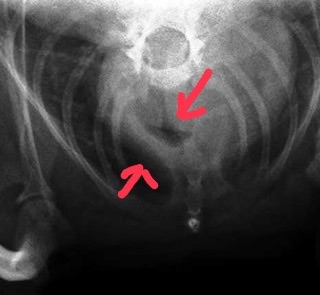

先日遠方から最近呼吸様式がおかしく苦しそうとの事で来院されました。その症例を紹介しますね。レントゲン検査にて重度頸部気管虚脱と診断して手術の日程を決めて帰られたのですがその道中で急変してその当日の手術となりました。気管虚脱は状況によっては急速に悪化することがあるので注意が必要です。